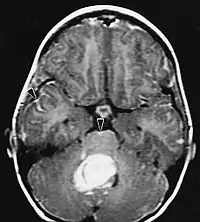

L'IRM montre généralement une lésion de contraste massive impliquant le cervelet. Comme mentionné ci-dessus, le médulloblastome a une forte propension à infiltrer localement les leptoméninges ainsi qu'à se propager à travers l'espace sous-arachnoïdien, impliquant les ventricules, la convexité cérébrale et les surfaces leptoméningées de la colonne vertébrale. Par conséquent, il est nécessaire de mettre en résonance tout l'axe crânio-spinal.

Les patients souffrent d'une variété de symptômes caractéristiques d'une lésion massive focale ou multifocale. L'IRM montre généralement des tumeurs avec un rehaussement de contraste homogène au sein de la substance blanche périventriculaire profonde. La multifocalité et le rehaussement inhomogène sont typiques des patients dont le système immunitaire est affaibli. L'analyse du lymphome du SNC est extrêmement importante dans le diagnostic différentiel de la néoplasie cérébrale. Il est à noter que l'administration de corticoïdes peut entraîner la disparition complète du rehaussement, rendant difficile le diagnostic des lésions. Par conséquent, si un lymphome du SNC doit être pris en compte dans le diagnostic différentiel, les corticoïdes doivent être évités à moins que l'effet de masse ne provoque un problème grave et immédiat chez le patient.

Les métastases cérébrales sont les néoplasmes intracrâniens les plus courants chez les adultes, étant dix fois plus fréquents que les tumeurs cérébrales primaires. Ils marchent à 20 jusqu'à 40 pour cent des adultes atteints de cancer et sont principalement associés au cancer du poumon et du sein et au mélanome . Ces lésions résultent de la propagation des cellules cancéreuses dans la circulation sanguine et surviennent le plus souvent à la jonction de la matière grise et blanche, où la section transversale des vaisseaux sanguins change, emprisonnant les embolies de cellules tumorales . 80 % des lésions surviennent dans les hémisphères cérébraux, 15 pour cent dans le cervelet et 5 pour cent dans le tronc cérébral. Environ 80 % des patients ont des antécédents de cancer systémique et 70 pour cent ont de multiples métastases cérébrales.

Des progrès significatifs ont récemment été réalisés dans le diagnostic et le traitement de ces lésions, entraînant une amélioration de la survie et du contrôle des symptômes. L'apparition des signes et des symptômes est similaire à celle d'autres lésions massives du cerveau. La méthode de diagnostic de choix est l'imagerie par résonance magnétique utilisant des produits de contraste.